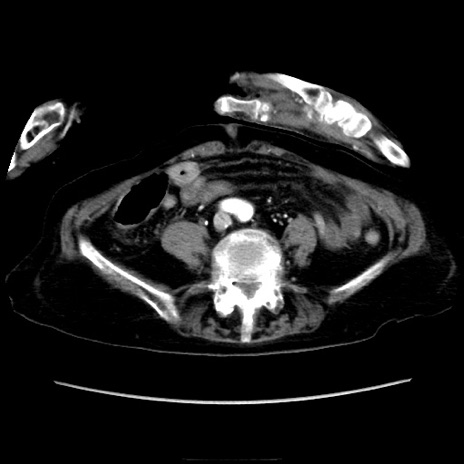

症例40(横断像)

【症例】90歳代女性

【主訴】腹痛・嘔吐

【現病歴】 食欲低下、嘔吐があり昨日他院受診。肺炎と診断され入院となる。入院後より腹部全体に圧痛あり。胃管留置され経過みていたが、症状持続するため、

当院転院となる。

【既往歴】胸椎圧迫骨折、胆石症

【身体所見】腹部:中央に激痛あり、圧痛あり、反跳痛不明

【データ】WBC 17100、CRP 18.82

横断像